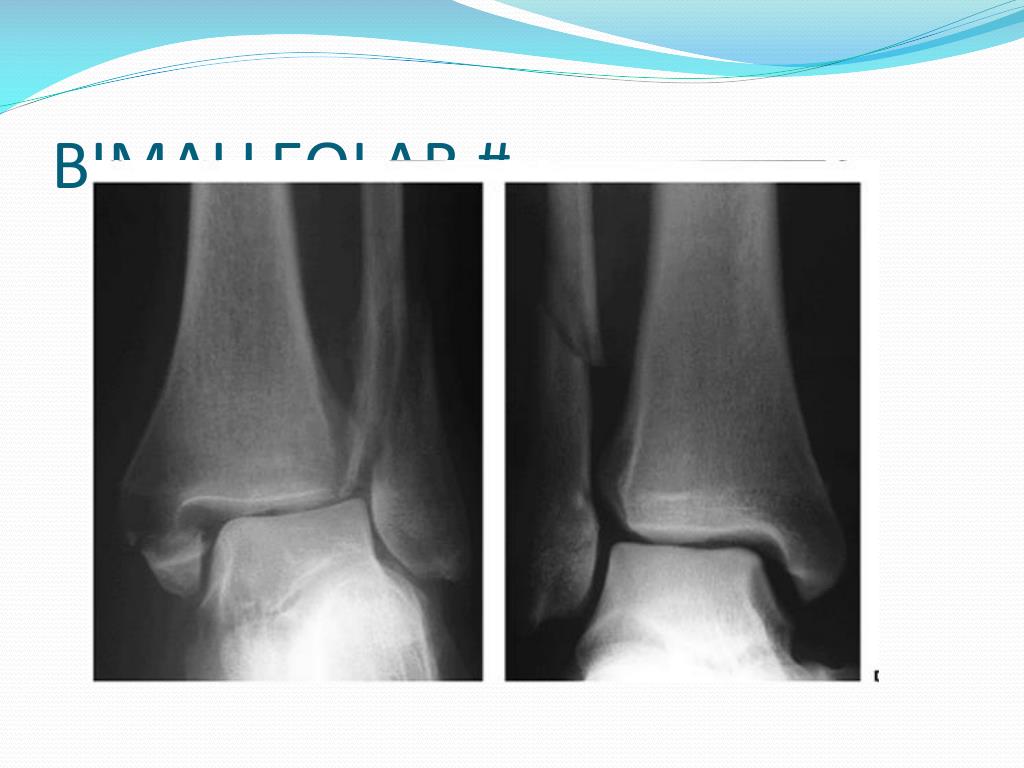

X rays . Prof.Dr.Mamdouh Lasheen. UPPER LIMB. # CLAVICLE. DISLOCATION SHOULDER. # SURGICAL NECK HUMERUS. S.C # HUMERUS. # HUMERUS. # HUMERUS WITH PLATE AND SREWS. ELBOW DISLOCATION. DAWOUD. DAWOUD. DAWOUD. DAWOUD. # BB FOREARM. LOWER LIMB. HIP DISLOCATION. THOMPSOM . AUSTIN MOORE.